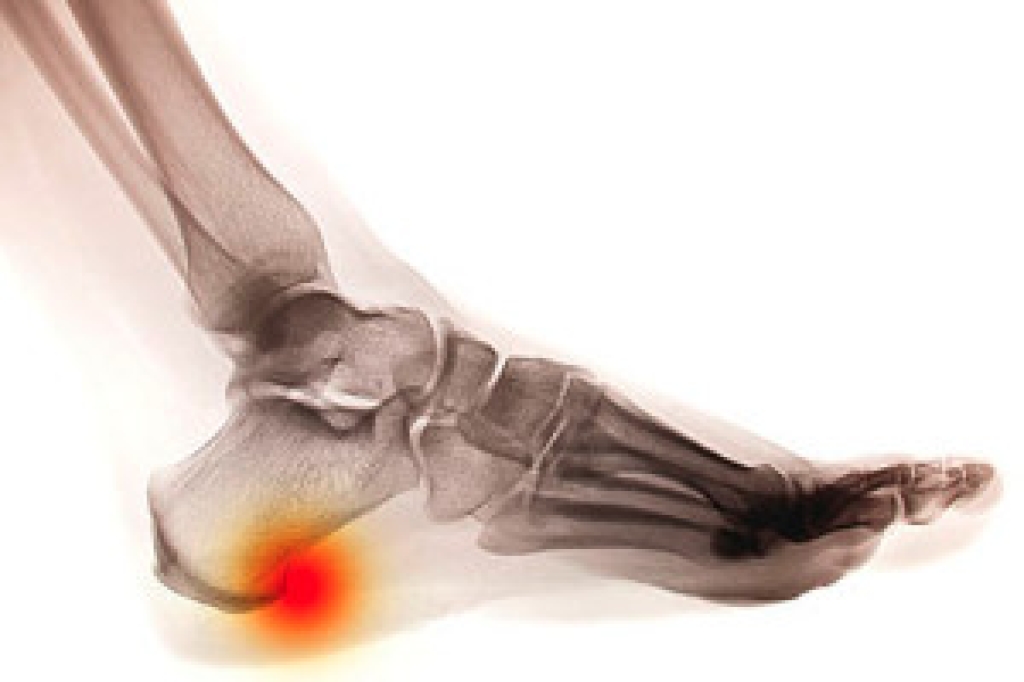

When the feet are properly cared for on a daily basis, certain foot conditions may be prevented from occurring. Athlete’s foot may be avoided when the feet are washed and thoroughly dried daily, especially between the toes. When a good moisturizer is applied, it may help to prevent cracked heels from developing. The importance of trimming the toenails properly is necessary in possibly preventing the painful condition known as ingrown toenails. Additionally, the feet will feel more comfortable when the correct size shoe is worn, and this can be accomplished if shoes are tried on in the afternoon when the feet are their largest. If you would like additional information about how to maintain proper foot care, it is advised to seek the counsel of a podiatrist.

It is best to check your feet regularly to make sure there are no new bruises or cuts that you may not have noticed before. For dry feet, moisturizer can easily be a remedy and can be applied as often as necessary to the affected areas. Wearing shoes that fit well can also help you maintain good foot health, as well as making it easier to walk and do daily activities without the stress or pain of ill-fitting shoes, high heels, or even flip flops. Wearing clean socks with closed shoes is important to ensure that sweat and bacteria do not accumulate within the shoe. Clean socks help to prevent Athlete’s foot, fungi problems, bad odors, and can absorb sweat.